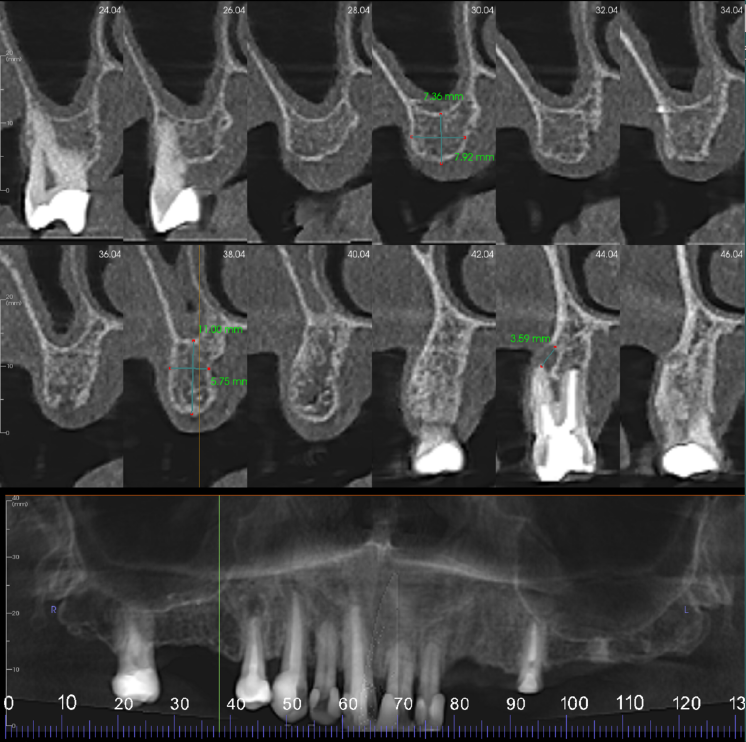

UR7-4 region cross sections at 2 mm intervals. Moderate loss in vertical bone height. The UR4 is root treated. The buccal root filling is short of the apex with 3-4 mm wide apical radiolucency. The palatal root canal is filled to the apex with 0.5-1 mm wide radiolucency

UL3-4 region cross sections at 3 mm intervals. Mild loss in vertical bone height. Moderate density cortical and trabeculae bone

UL5-7 region cross sections at 3 mm intervals. Moderate loss in vertical bone height. Moderate density cortical and trabeculae bone

UL1 showing external root resorption, mostly on the palatal side of the root. Approximately a third to half of the root resorbed. The root may be partially ankylosed to the bone

UL7 edentulous ridge. Well defined radiopacity extending from the alveolar bone crest to the sinus floor